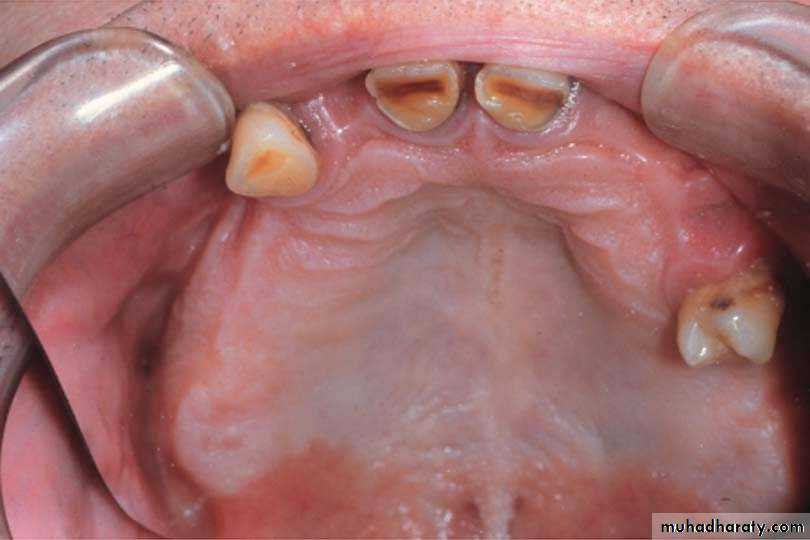

Anatomical landmarks of the maxilla & maxillary arch

Maxillary anatomical land marks

Maxilla & maxillary arch